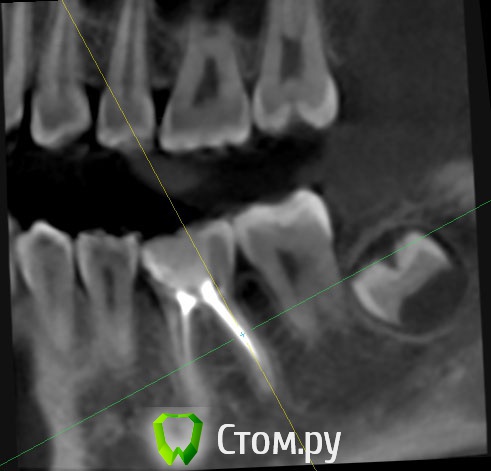

Selena_14 Опубликовано 8 апреля, 2014 Поделиться Опубликовано 8 апреля, 2014 Здравствуйте.Ребенку 14 лет. Два с половиной года назад зуб депульпировали, через год перелечивали. Сейчас частично разрушилась стенка зуба ниже десны на 3мм. Зуб ребенка не беспокоит. Можно ли сохранить зуб? К сожалению, есть только снимок полугодовой давности. Ссылка на комментарий

Korel Опубликовано 8 апреля, 2014 Поделиться Опубликовано 8 апреля, 2014 Сейчас частично разрушилась стенка зуба ниже десны на 3мм. Субъективно. Сделайте снимок сейчас (а не через пол года ) , тогда можно поговорить более предметно. Ссылка на комментарий